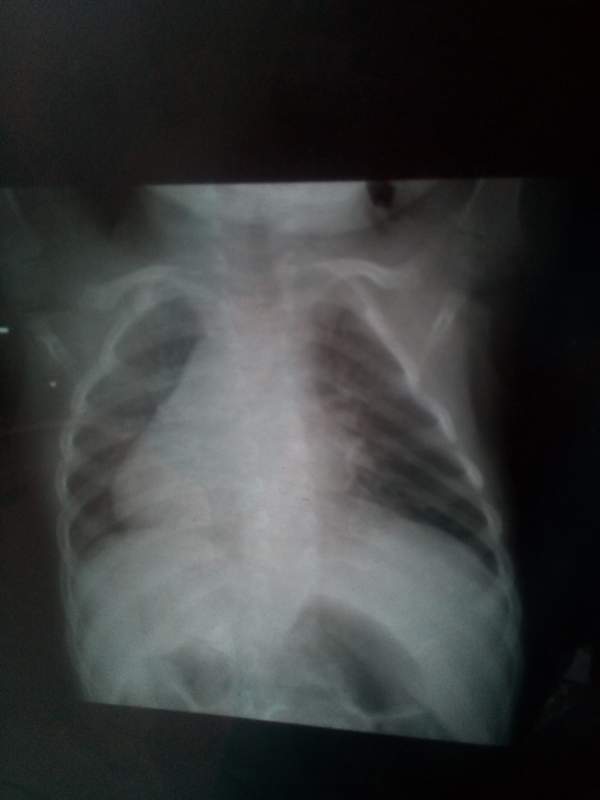

ÃÃÃÃÒòÖÎÁÆÑÓÎó£¬ÏÖ²¡Çé¼ÓÖØ£¬ÃæÁÙ̱»¾£»Õ÷Çó¸÷λ³æÓÑÌá³ö±¦¹óµÄÒâ¼û£¬½«¸Ð¼¤²»¾¡